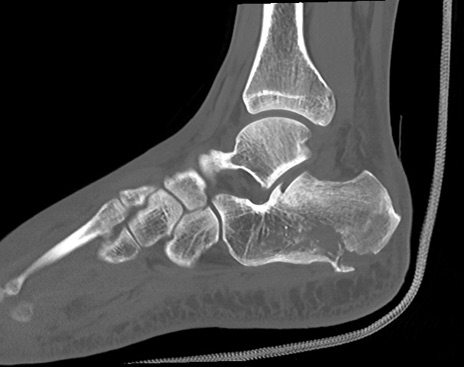

症例37 左足関節CT(矢状断像)

左足関節CT

3D再構成